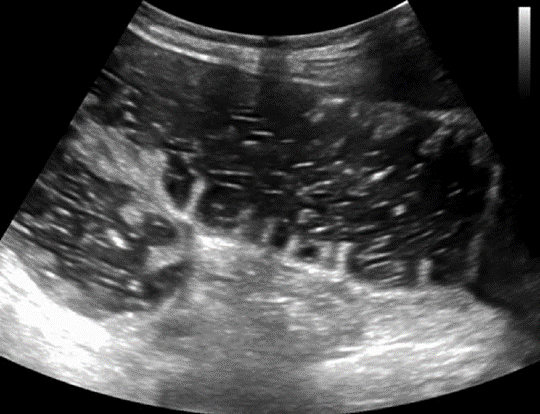

Sonographic findings of SBO include dilated bowel with a diameter of greater than 2.5 cm, fluid-filled loops of bowel, decreased peristaltic movement, increased wall thickness, prominent valvulae conniventes, and a collapsed colonic lumen [40, 41] (Fig. 7).

Free fluid in the peritoneal cavity is associated with higher-grade obstruction and predicts need for operative intervention [42]. A transition point is often difficult to visualize, but POCUS can locate and identify the potential cause of obstruction, such as hernia, intussusception, masses, and signs of ischemia [43]. Evaluating SBO is not a core application of POCUS; it is a suitable modality for initial imaging evaluation and early management of SBO.